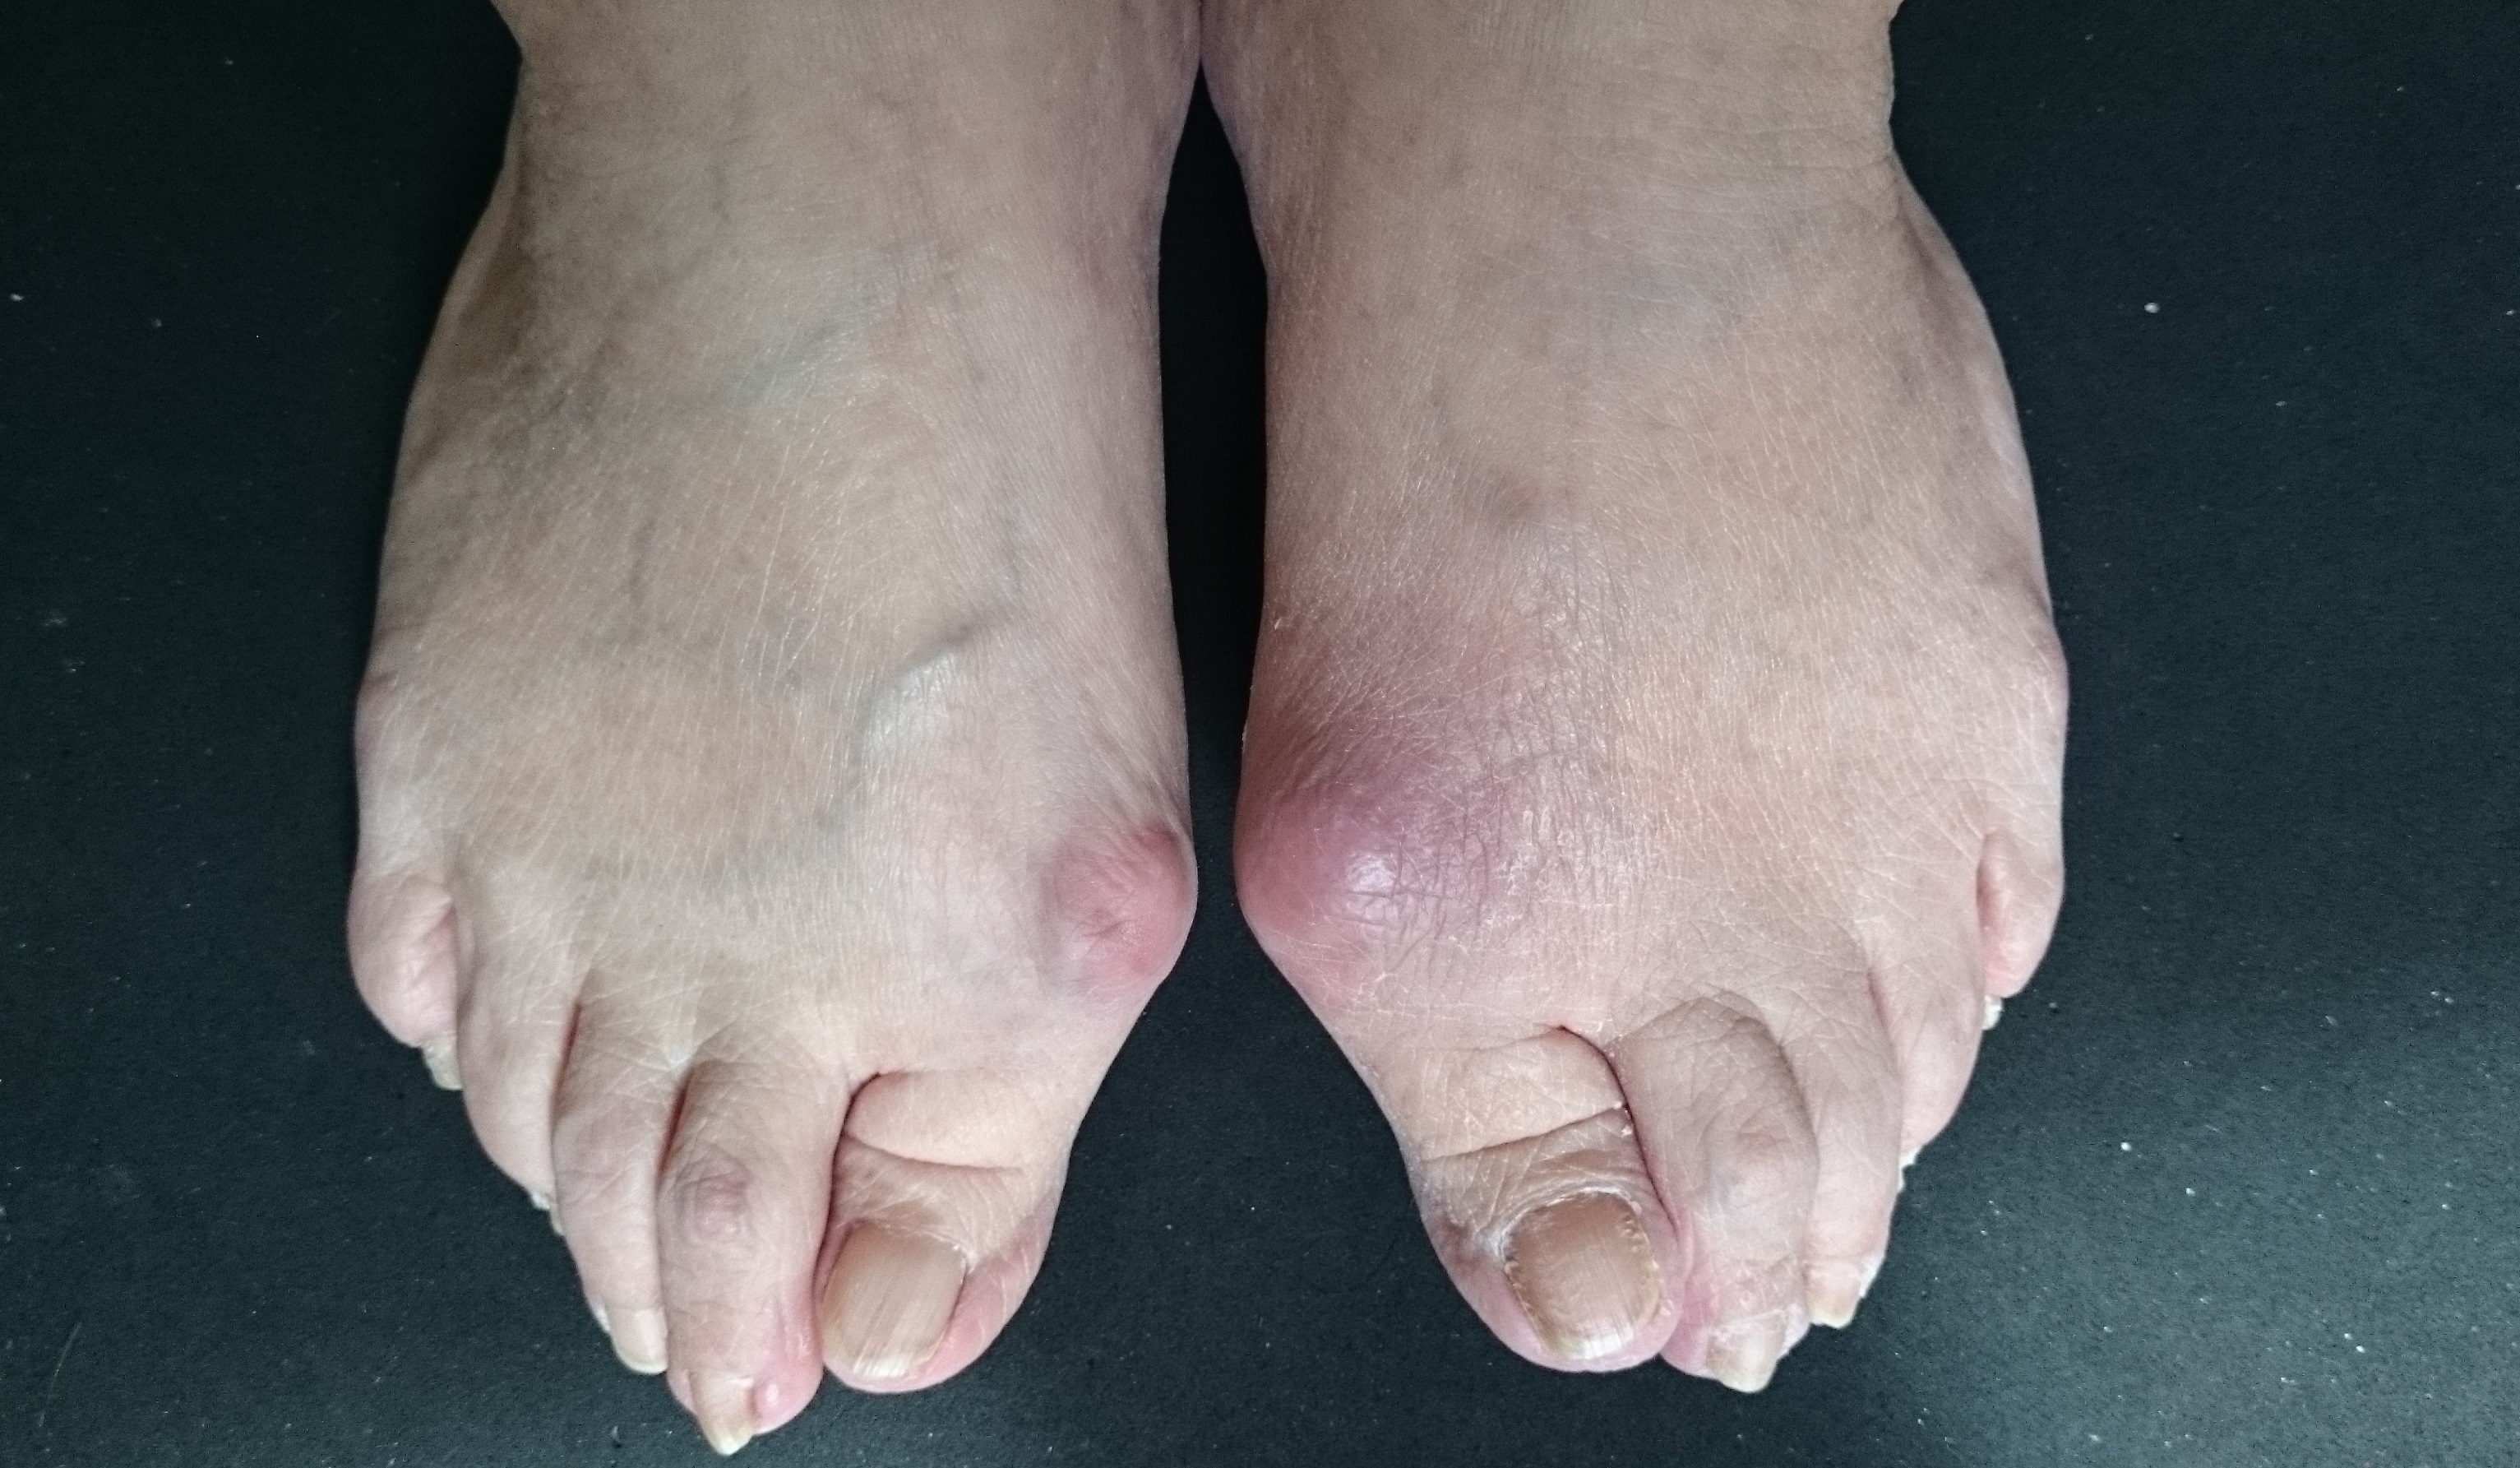

ご要望、足の痛み、靴の悩み、外反母趾、リウマチなどの